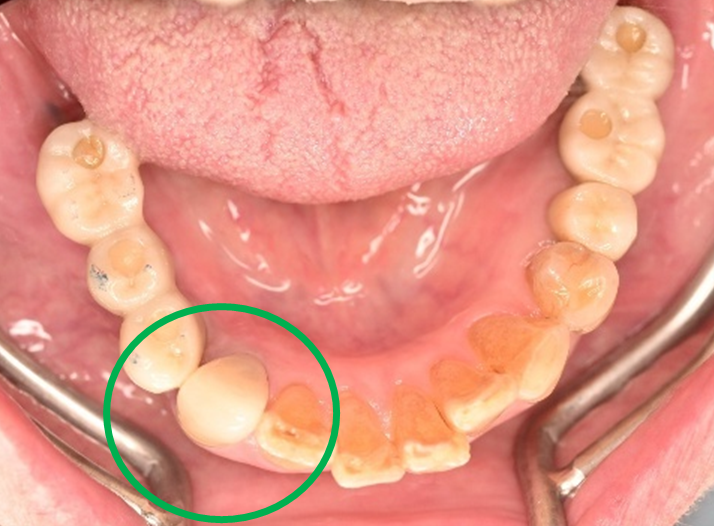

女性 Yさん 60代 (オールセラミック冠)

主訴

以前治療した右下の犬歯が、虫歯になり色が変わってきているので、治したい。

治療内容

根管治療をし、オールセラミック冠を被せました。

所感

神経が取り除かれ、歯自体が変色し、虫歯になっていました。根管治療をし、ファイバーコアを入れ、オールセラミック冠を被せました。

オールセラミック冠1本(失活歯):¥104,500(税込)

Before

After